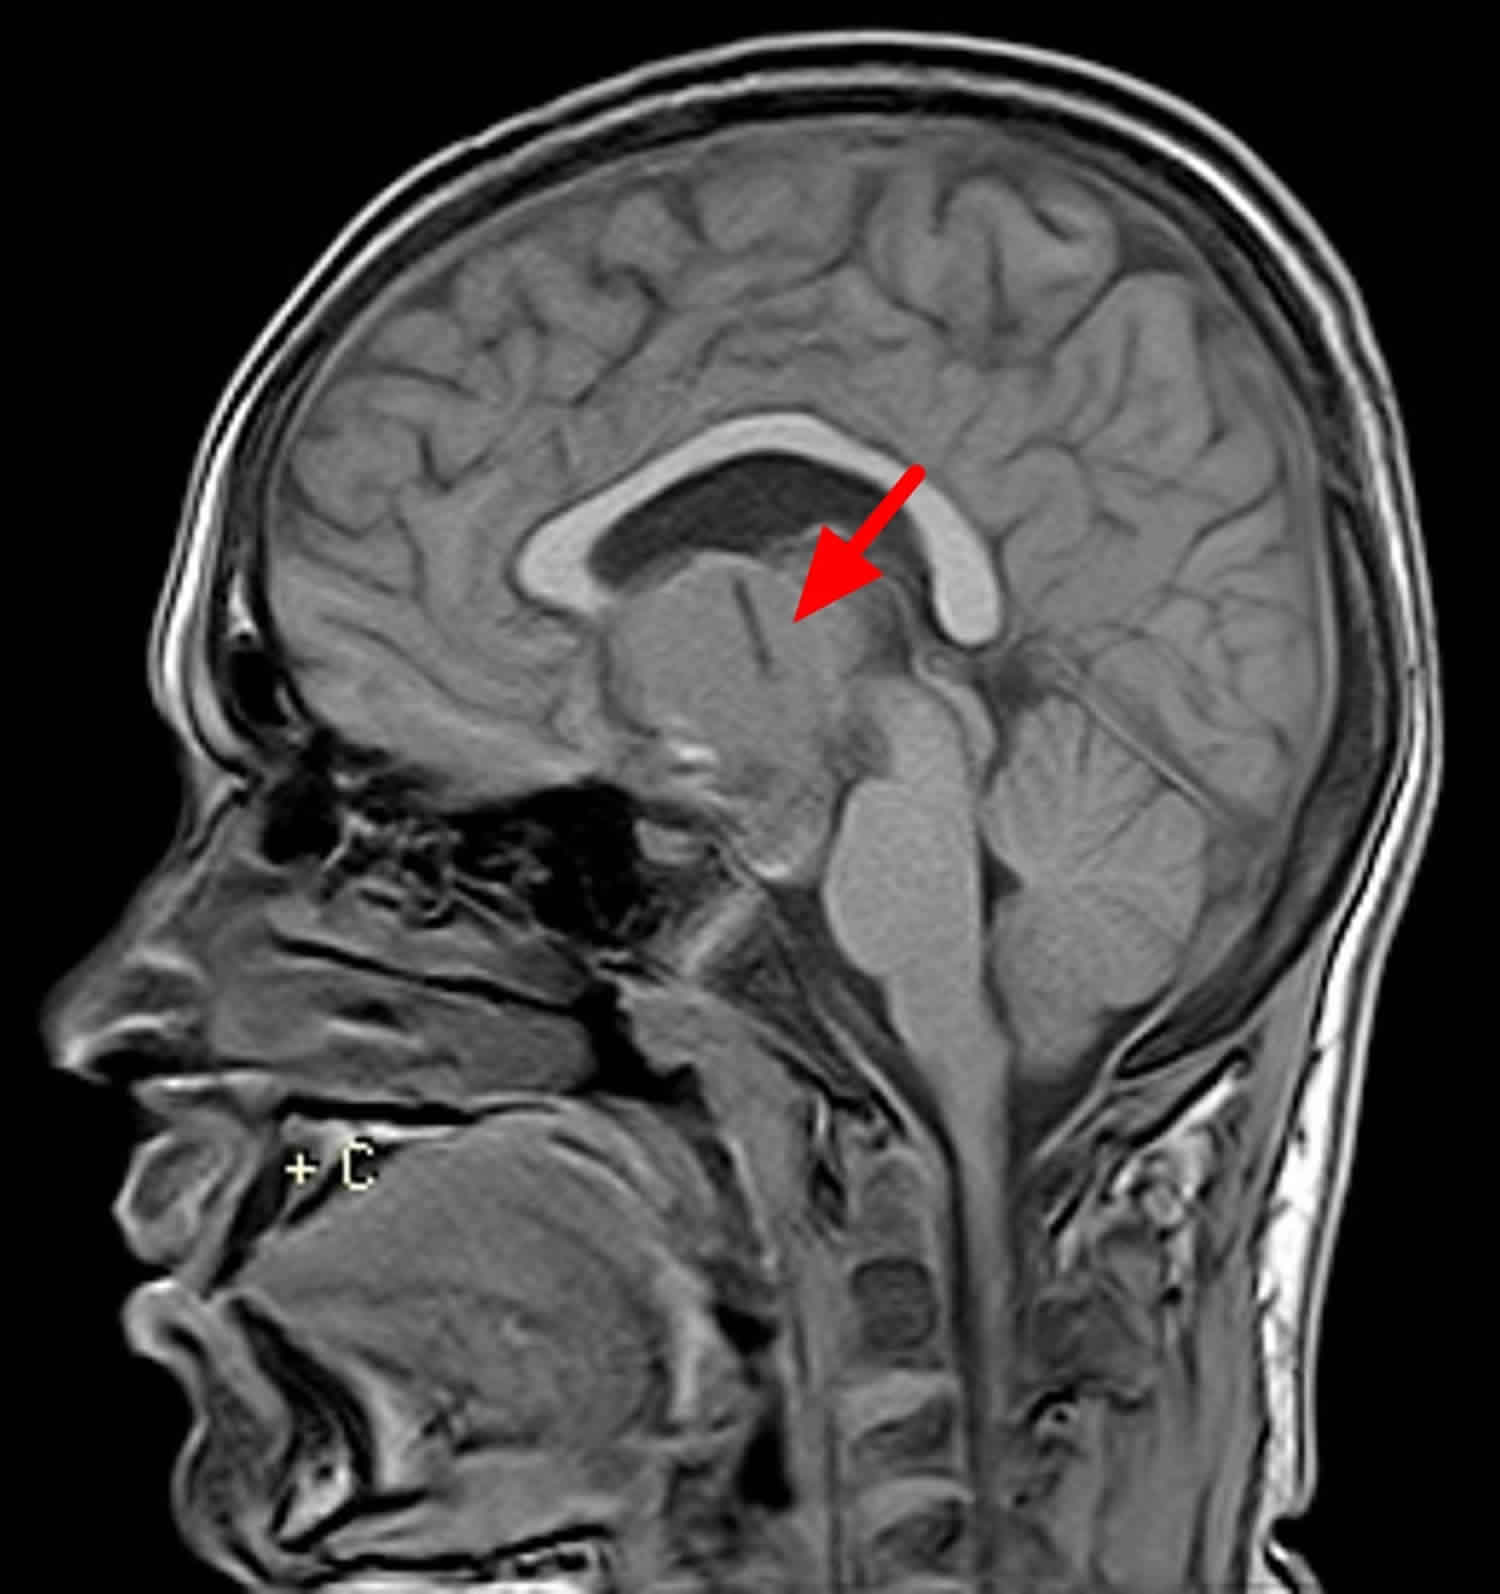

颅咽管瘤是一种中枢神经系统肿瘤。中枢神经系统肿瘤可以是癌性的,也可以是良性的。癌性肿瘤是恶性的,这意味着它通常生长迅速,可以扩散到身体的其他部位。良性肿瘤意味着肿瘤通常生长较慢,但不会扩散。颅咽管瘤被认为是良性肿瘤,这意味着它通常生长缓慢,很难扩散。颅咽管瘤是一种通常发生在垂体上方的肿瘤。位于大脑底部的腺体大约有豌豆大小,控制着许多重要的功能。

由于它们靠近下丘脑、脑底动脉环、视交叉、视神经、脑下垂体和脑下垂体柄,所以受到了挑战。下丘脑和垂体柄通常是具有挑战性的解剖平面,试图保存这些结构对降低切除相关的风险很重要。颅咽管瘤倾向于将周围的神经脉管系统从中心位置向上和向外推。传统上,开放颅底入路一直受到限制,因为需要进行大量的脑回缩,而且需要通过大血管周围的小手术窗口。虽然全切术(GTR)为患者提供了较高的无进展生存率(PFS),但通过内镜颅底手术(ESBS)和经颅手术(TCS)来保留下丘脑和/或垂体功能的故意次全切除已变得更为常见,是在儿科患者中。